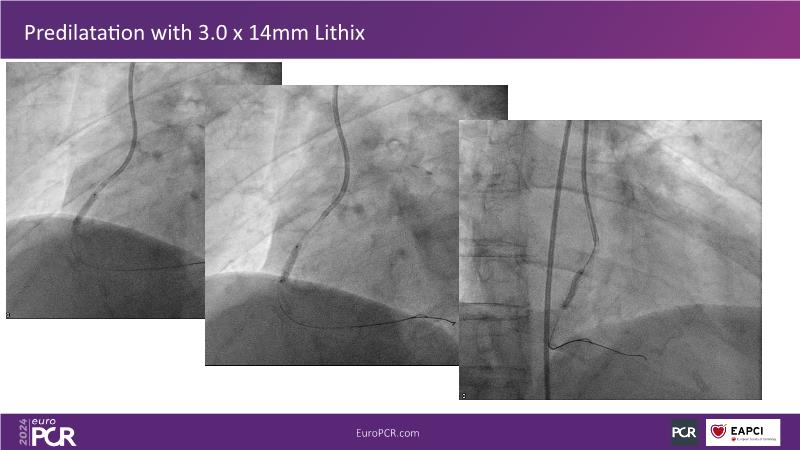

Follow this session to learn about the novel HC-IVL system, its application for moderate to severe calcified lesions, and procedural tips. The LithiX Hertz Contact IVL addresses unmet needs in coronary artery calcification by offering a simplified workflow with fewer devices and effective treatment for difficult lesions. Its novel design ensures safety and efficacy, with the PINNACLE I study's primary outcomes expected to confirm its effectiveness.

- To learn tips and tricks of the HC-IVL procedure